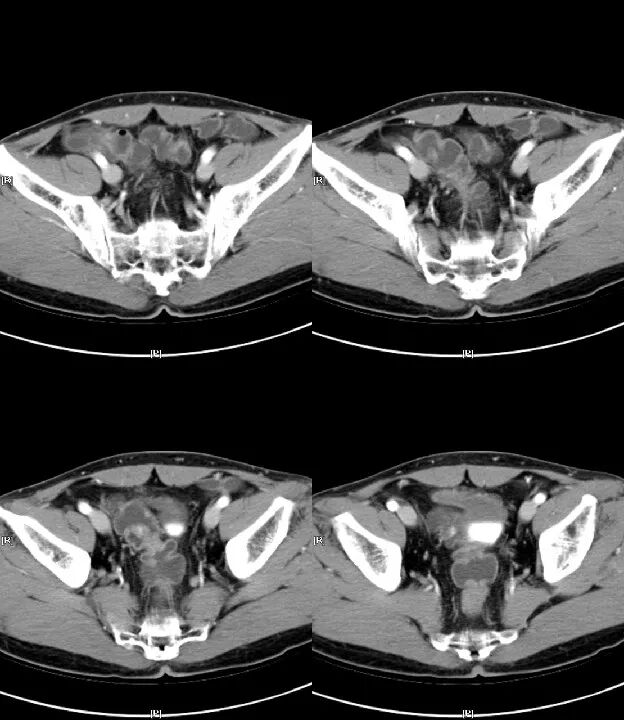

气腹

腹腔内存在游离气体的现象。多由胃肠道穿孔等所致,表现为腹部叩诊肝浊音区消失,病人站立作X线检查时,可见膈下有游离气体,如因消化性溃疡或伤寒等并发急性胃或肠穿孔时,须立即手术治疗。因诊断和治疗上需要将气体注入腹腔内所致的气腹,称人工气腹。